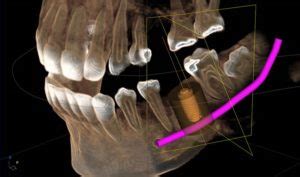

- Planificación preoperatoria: Realizar una evaluación exhaustiva de la posición de la muela del juicio y su relación con el nervio mediante radiografías y tomografías computarizadas (TAC).

- Técnica quirúrgica cuidadosa: Utilizar técnicas microquirúrgicas y fresar el hueso con precaución para evitar dañar el nervio.

- Coronectomía: Remover solo la corona de la muela del juicio, dejando las raíces cerca del nervio para evitar lesionarlo.

La “técnica de la usura” es extensible a otras piezas dentarias incluidas en que concurra un alto riesgo de lesión del dentario inferior. El Dr. Yves Commissionat Médico Estomatólogo, explicaba en su articulo publicado en 1995 el procedimiento y su utilidad. Esta técnica se basa en la observación clínica y radiológica en pacientes que portan restos radiculares “bien tolerados” tanto en su lecho óseo como en su recubrimiento de encía, que permite pensar en esta actuación para evitar la lesión del nervio dentario inferior en situaciones de alto riesgo.

Las posibles complicaciones tras la coronoidectomía son: la migración, movilidad o la erupción de la raíz.